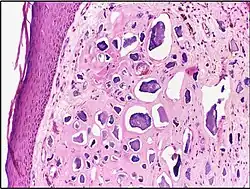

![]() | Renal cell carcinoma | Micrograph of clear cell renal cell carcinoma showing cells with clear cytoplasm, typically arranged in nests and nuclear atypia. | Category: Histopathology of renal cell carcinoma | Renal cell carcinoma |